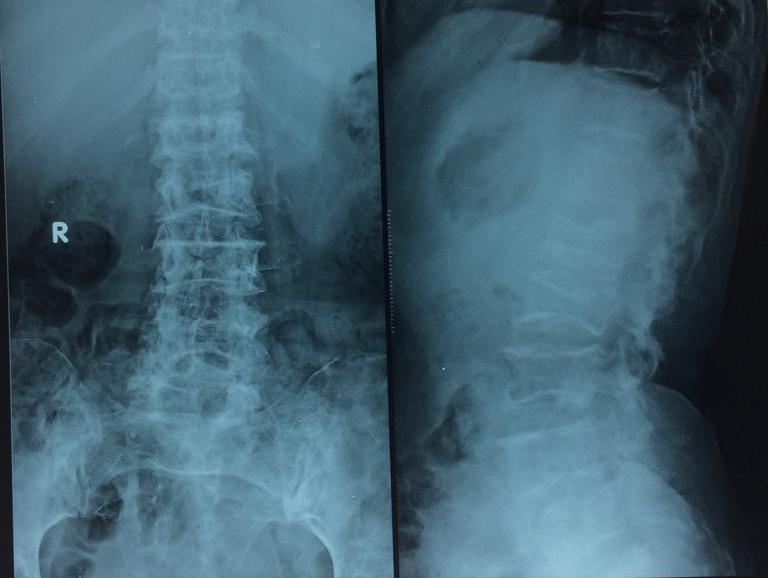

Investigations :Labs : anemia hb 4.5 with mcv 102.7 ,mch 30.8Esr 30, Platelet 45000 creatinine 2.2 with globulin 11.2 g/dl, albumin 2.6 .Corrected ca 10.In view of hypergammaglobulinemia, anemia, and renal dysfunction, there was a suspicion of multiple myeloma.X-ray skull and vertebrae were taken which showed punched out lesions in the skull and lytic lesions in vertebrae with fishbone appearance. Fig 1 and Fig2 Bone marrow aspiration showed plasma cells >50% of the marrow s/o multiple myelomaRenal dysfunction improved with adequate hydration and correction of anemia was done via blood transfusions.She is planned for chemotherapy .